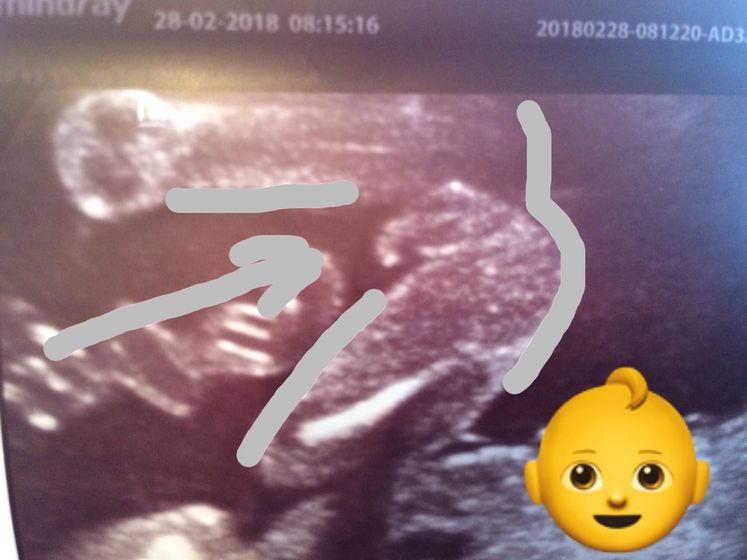

5 дней соображала и разгадывала, что же это на снимке изображено))) и вот спустя время догадалась, так это же сыночка достоинства!^.^

Мальчик мальчик, поздравляю!

ну у нас пиписька по узи по другому была, ровная а у вас как крючок))